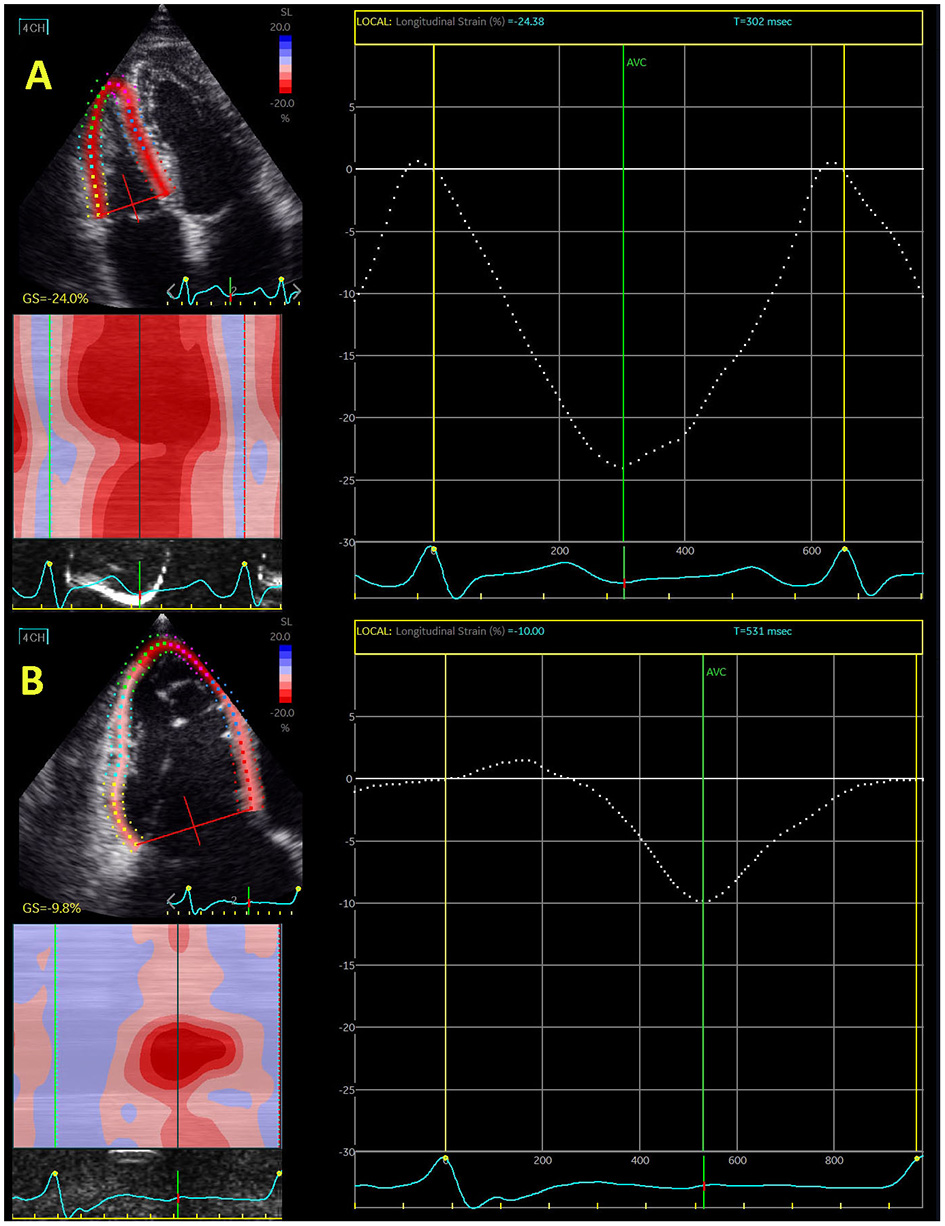

The evaluation of RV longitudinal strain is also performed in 4-chamber view, which certainly represents an advantage because it does not demand additional time for acquisition (Figure 1). RV wall is significantly thinner than in the left ventricle (LV) and consists of only two layers that are predominantly longitudinally and obliquely directed in the free wall (17). The deep subendocardial fibers have longitudinal direction from base to apex, while the superficial subepicardial fibers normally have circumferential direction, parallel to the AV groove (19), but they turn obliquely as they approach to the apex of the heart and continue onto the LV. The continuity of RV and LV fibers significantly contributes to ventricular interdependence (19), which is important for both RV and LV function.

Figure 1

Echocardiography-derived right ventricular global longitudinal strain in control subjects (A) and patient with severe functional tricuspid regurgitation (B).

Isolated or concomitant functional tricuspid regurgitation has been extensively investigated in last decade. It has been shown that tricuspid regurgitation significantly deteriorated the outcome in patients with mitral regurgitation. However, surgical intervention seems not to improve RV function in these patients (42). Interventional “edge-to-edge” repair significantly increased interest for predictors that may improve outcome after this intervention. Hirasawa et al. (67) reported that reduction of RV free-wall longitudinal strain was proportional to the level of tricuspid regurgitation. Figure 1 shows difference in RV global longitudinal strain between control subjects and patients with severe functional tricuspid regurgitation.